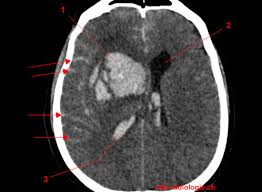

TDM (Scanner) Cérébral: L’Hémorragie apparait comme une hyperdensité spontannée (blanc) dans le parenchyme ou les ventricules

- Hémorragie cérébro-méningée avec inondation ventriculaire: